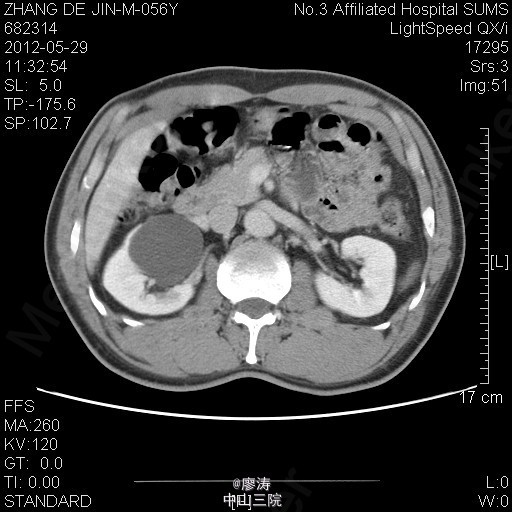

患者男,56岁,因腰痛2年到当地医院检查,当地医院彩超提示:右肾下部无回声区,考虑肾囊肿可能性大,右肾上盏局限性积液,余未见明显异常。为进一步治疗来我院就诊,行腹部CT检查提示右肾巨大囊肿,压迫右侧肾盂及中下盏。

腹部CT检查提示右肾巨大囊肿